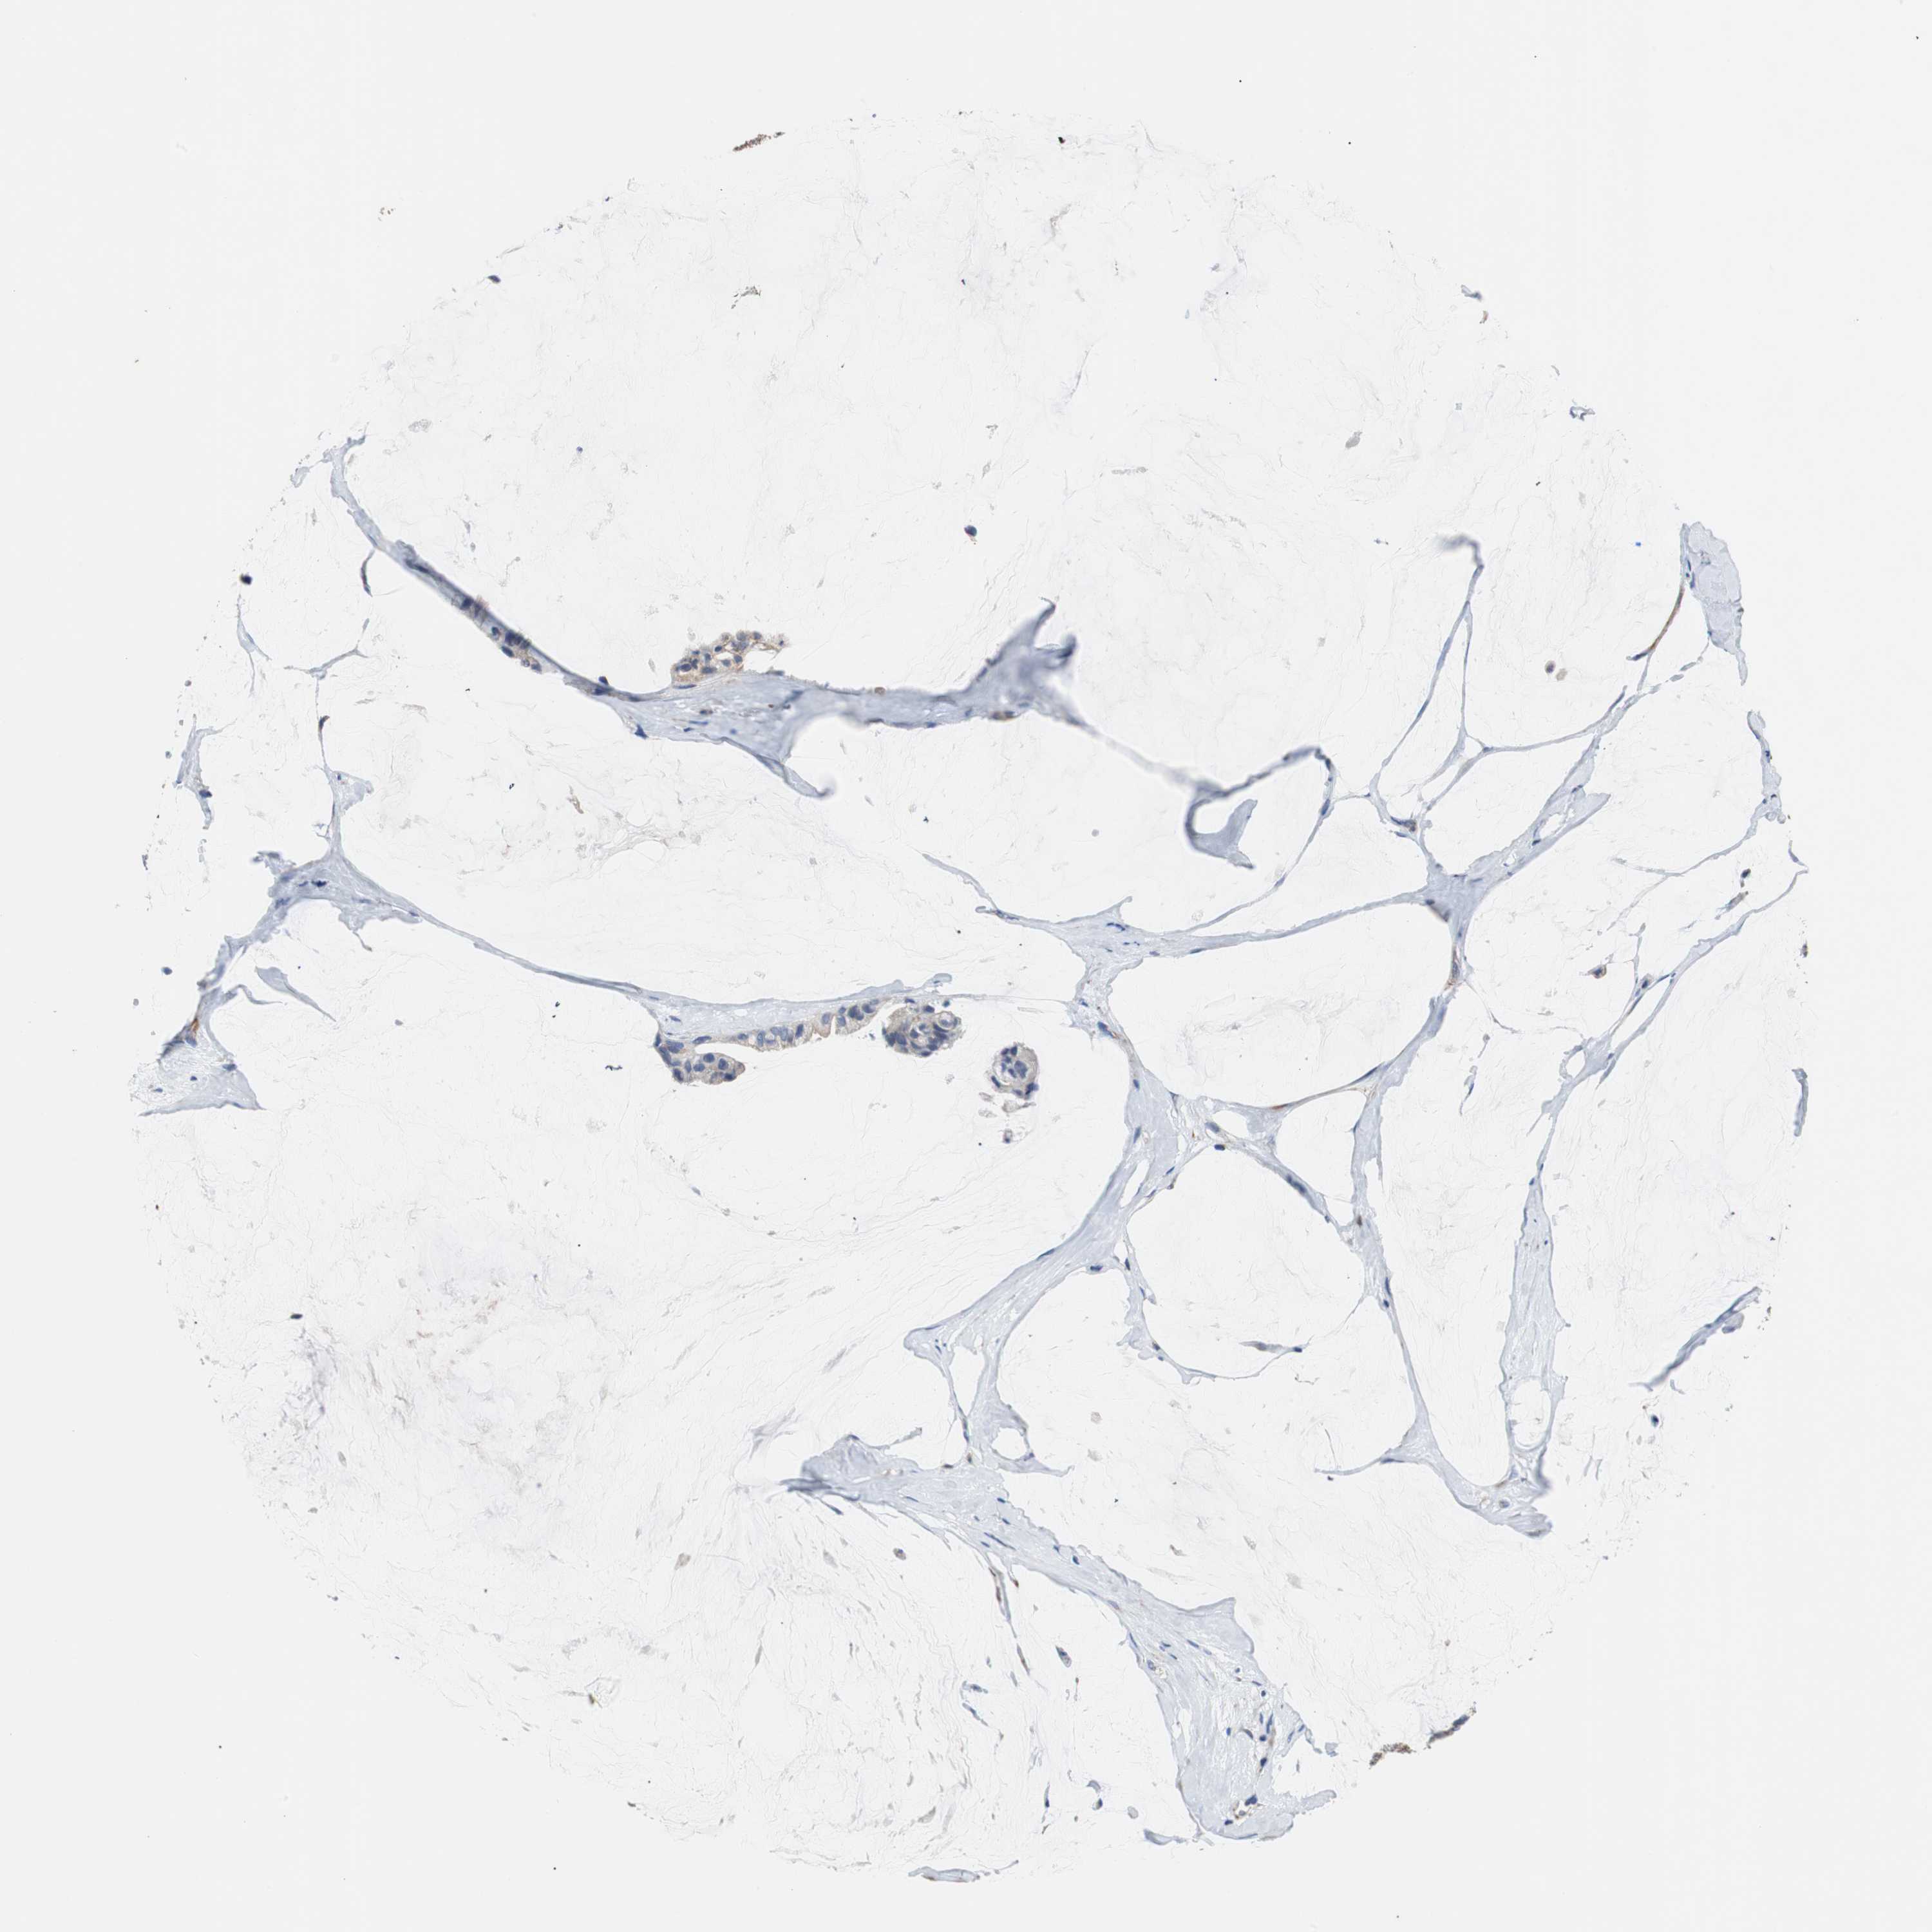

OVARIAN CANCER - Protein expressioni

A mouse-over function shows sample information and annotation data. Click on an image to view it in a full screen mode. Samples can be filtered based on level of antibody staining by selecting one or several of the following categories: high, medium, low and not detected. The assay and annotation is described here.

Note that samples used for immunohistochemistry by the Human Protein Atlas do not correspond to samples in the TCGA dataset.

Antibody stainingi

Antibody staining in the annotated cell types in the current human tissue is reported as not detected, low, medium, or high, based on conventional immunohistochemistry profiling in selected tissues. This score is based on the combination of the staining intensity and fraction of stained cells.

Each image is clickable and will lead to virtual microscopy that enables deeper exploration of all samples and also displays staining intensity scores, fraction scores and subcellular localization as well as patient and tissue information for each sample.

Antibody HPA006277

Cystadenocarcinoma, serous, NOS